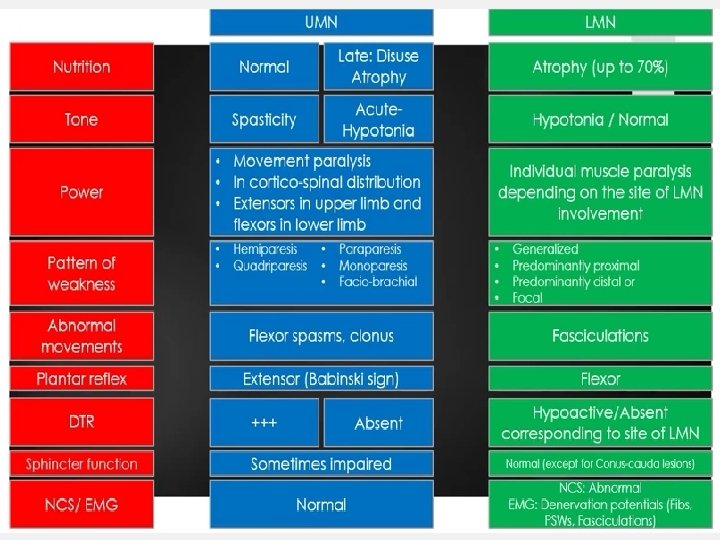

• UPPER MOTOR NEURONS (UMN) start from cerebral cortex, passes through internal capsule, corticospinal tracts, and ends at cranial nerve nuclei in brain stem or anterior horn cells of spinal cord at different levels. The axons of upper motor neurons are contained within the pyramidal system, which is composed of the corticospinal (pyramidal) and corticobulbar tracts. • LOWER MOTOR NEURONS (LMN) start from nuclei of cranial nerves or anterior horn cells of spinal cord, extend through cranial /spinal nerves and ends at motor end plate of concerned muscle.

Pyramidal Drift Of An Upper Limb Normally, the outstretched upper limbs are held symmetrically, when the eyes are closed. With a pyramidal lesion, when both upper limbs are held outstretched, palms uppermost, the affected limb drifts downwards and medially. The forearm tends to pronate and the fingers flex slightly. This sign is often first to emerge, sometimes before weakness and/or reflex changes become apparent.

Weakness And Loss Of Skilled Movement Ø A unilateral pyramidal lesion above the decussation in the medulla causes weakness of the opposite limbs. Ø When acute and complete, this weakness will be immediate and total, a hemiplegia, e. g. following an internal capsule infarct. Ø With slowly progressive lesions (e. g. a hemisphere glioma) a characteristic pattern of weakness emerges – a hemiparesis. Ø There is also loss of skilled movement – fine finger and toe control diminishes.

Changes In Tone And Tendon Reflexes Ø An acute lesion of one pyramidal tract (e. g. internal capsule stroke) causes initially FLACCID paralysis with loss of tendon reflexes. Ø Increase in tone follows, usually within several days due to loss of inhibitory effects of the corticospinal pathways and an increase in spinal reflex activity. Ø SPASTICITY is characterized by sudden changing resistance to passive movement – the clasp-knife effect. Ø Relevant TENDON REFLEXES become exaggerated; Ø CLONUS may emerge.

Changes In Superficial Reflexes Abdominal (and cremasteric) reflexes are abolished on the side affected. The Babinski sign.